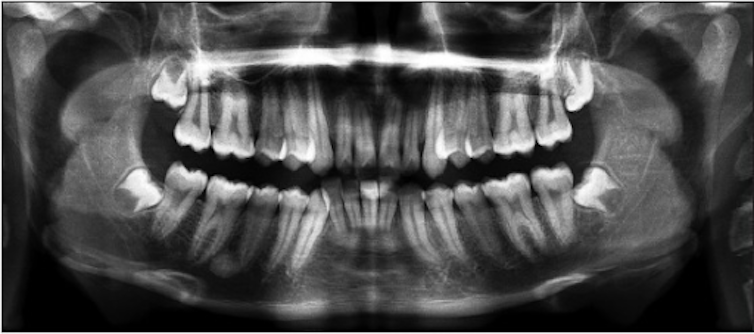

For children and teenagers, such an analysis can be carried out by examining X-rays. Growth and development are predictable processes, and milestones occur in a particular order. This is the reason that a tooth such as the first adult molar is also known as the “six-year molar,” because it generally erupts in everyone around age 6, give or take.

The analysis proceeds the same way whether we’re examining the X-rays of a living or deceased person. Essentially, we compare the stage of growth shown in the X-ray to existing growth charts from children and teenagers of known ages.

Sometimes, the estimated age range might include ages below and above 18. Take the development of the wisdom tooth, something we often look at when estimating age of older teenagers and young adults. But the development of this tooth is extremely variable, ranging from never developing at all to erupting anywhere from the mid-teens to early 20s. In such cases, how would a final decision of adult or minor status be made?